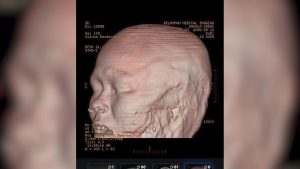

Tonight, the family of accident victim Ireni Savala is appealing to the public for help as she faces a long and challenging recovery. Savala was found critically injured along the roadside in Big Falls on December seventeenth, 2025, after she was reportedly thrown from a motorcycle and left there. According to her relatives, her injuries are severe and will require extensive medical treatment, including facial reconstruction surgery, after she lost one of her ears. Earlier today, News Five spoke with her sister, Francine Savala, who provided an update on Ireni’s condition and the ongoing fundraising efforts.

“Yes ma’am. She is awake. She is recovering, but a part of her face, left side of her face has been torn off, including her left ear. So far my sister is just saying the person that she was with the night the accident happened. She cannot fully remember the incident, everything. I think because of the trauma she got to her head. She has like about five bursts on her head. So I think the trauma that she had, the hit on her head that caused her to, she cannot remember the incident fully.” We want to seek further medical treatment so that the doctors in PG told us that that she would need like a surgery to her face to replace, take a part of her, some part of her body, like a piece of skin and replace it on her face. And then maybe a plastic surgery for her ear.”